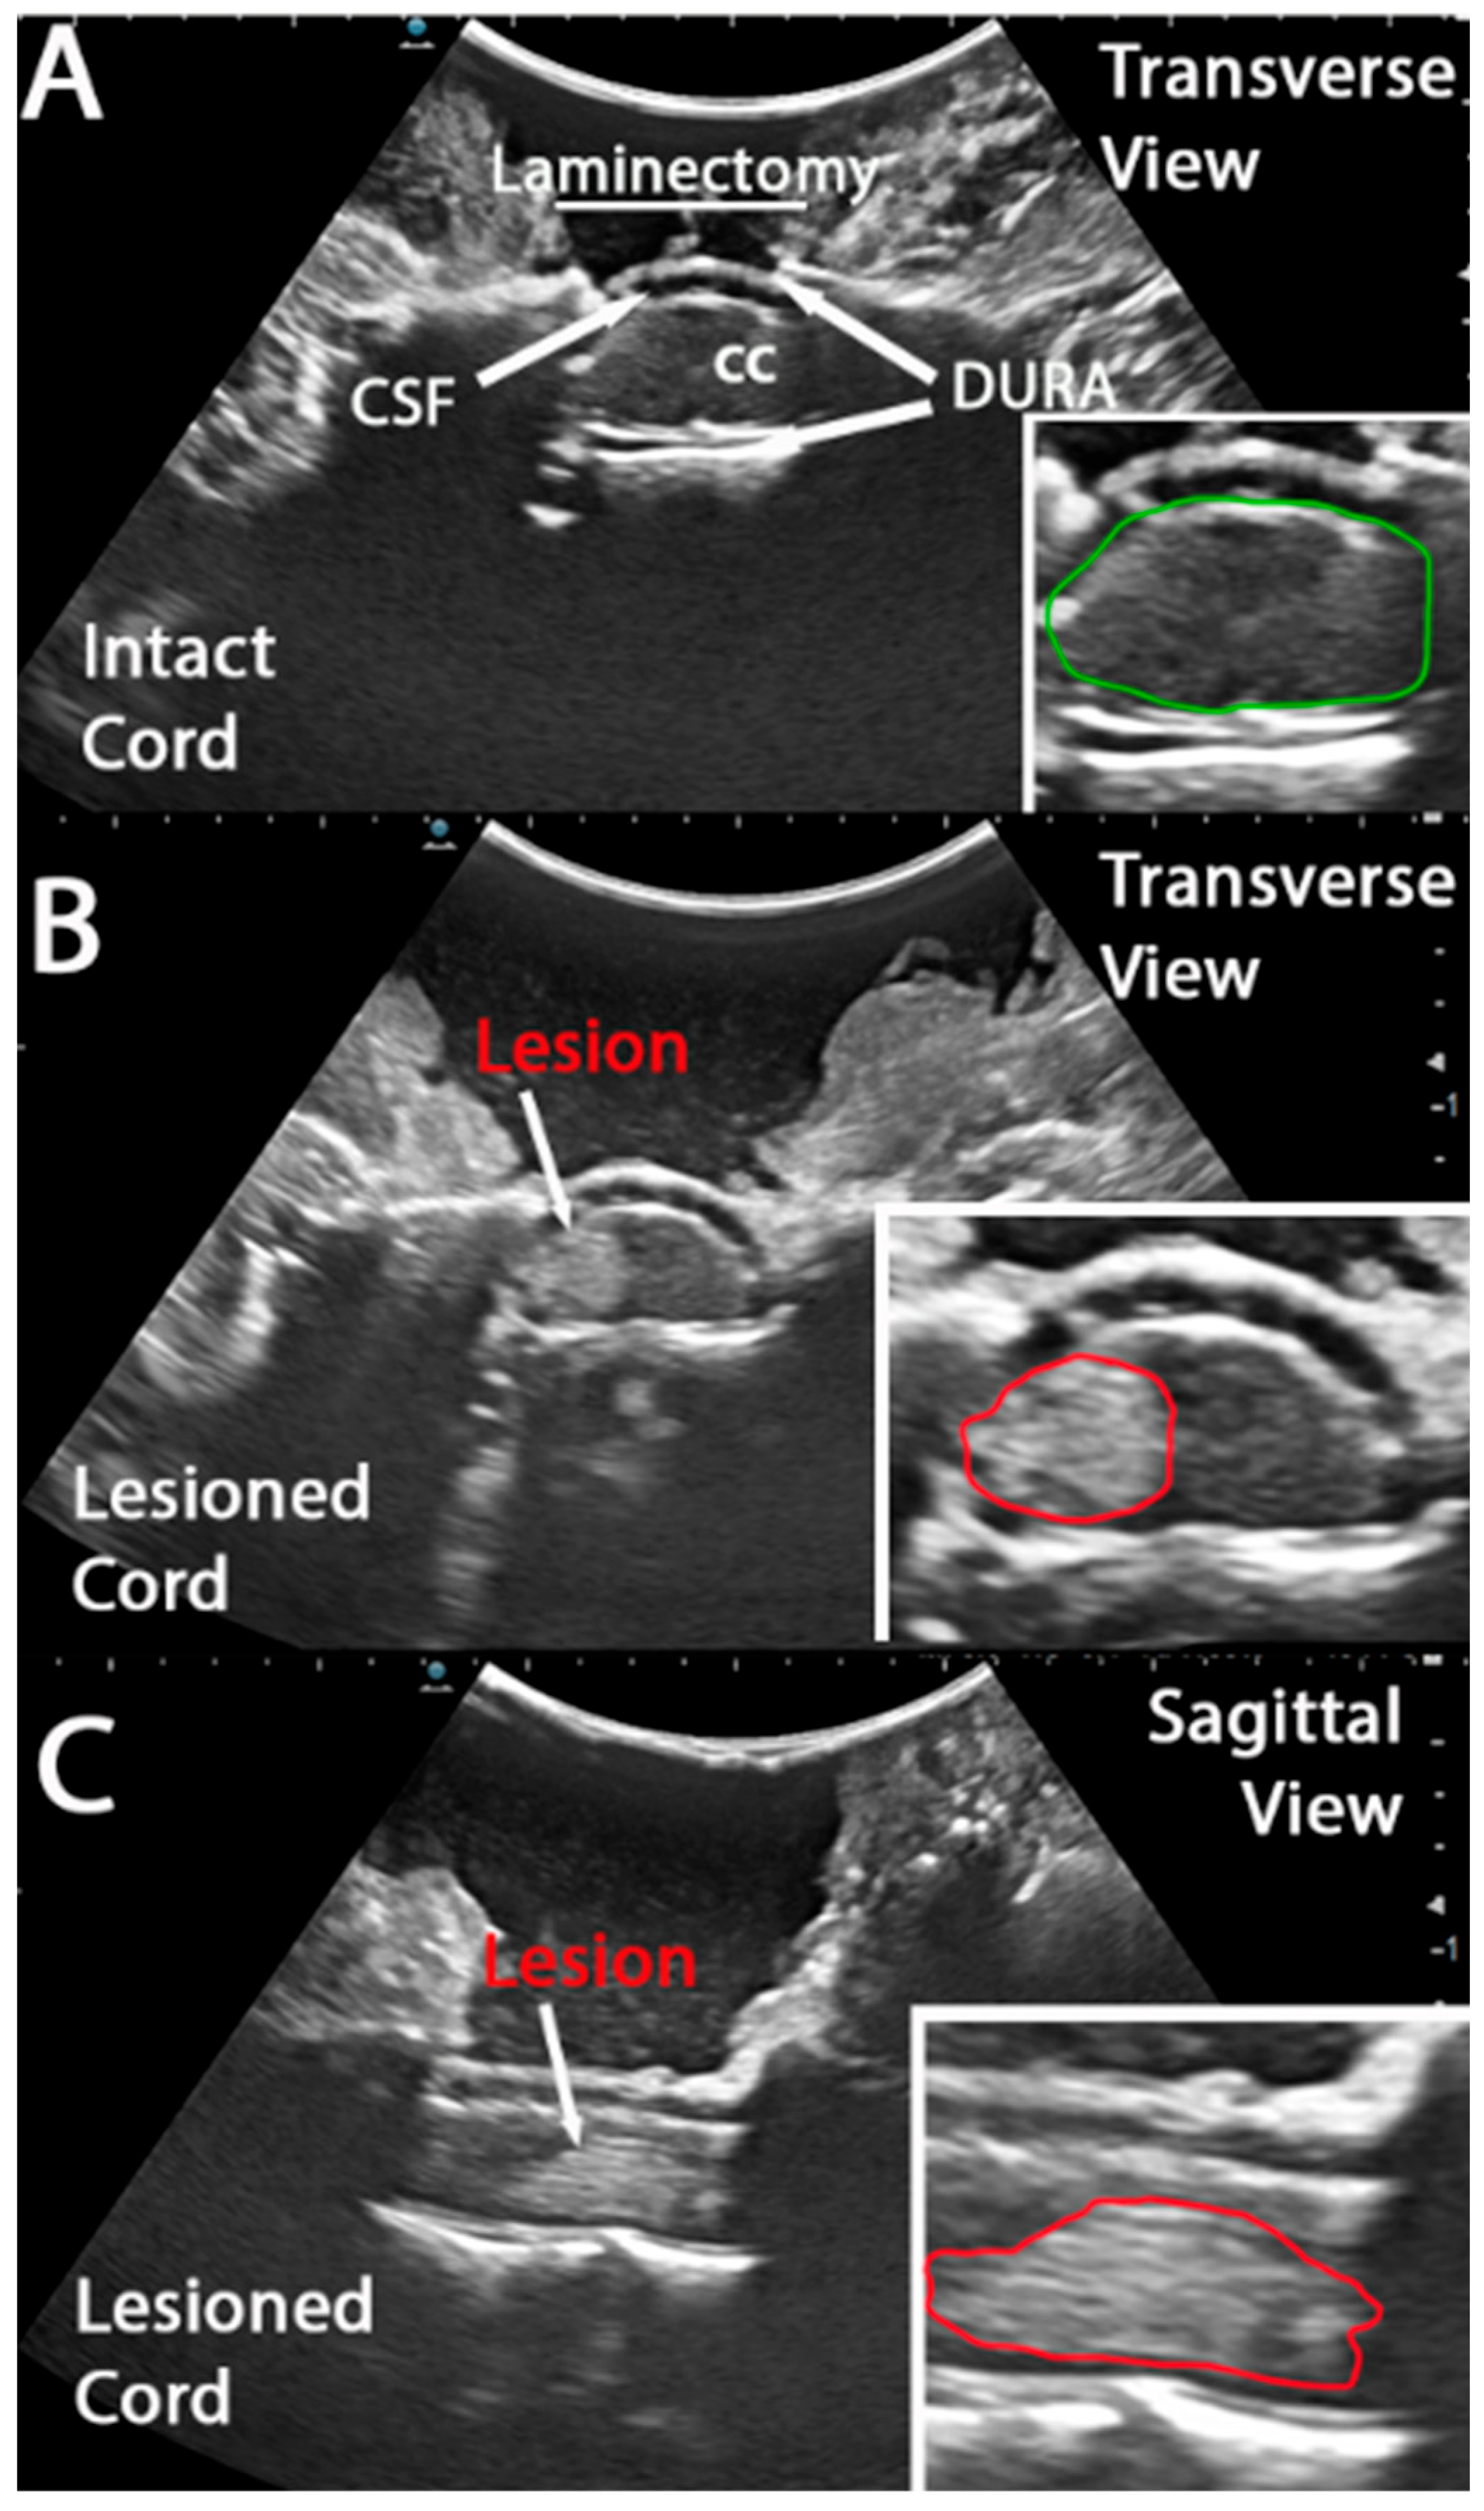

3.1. Intra Operative Ultrasound to Visualize a Hyper Acute Timepoint in a Hemicontusion